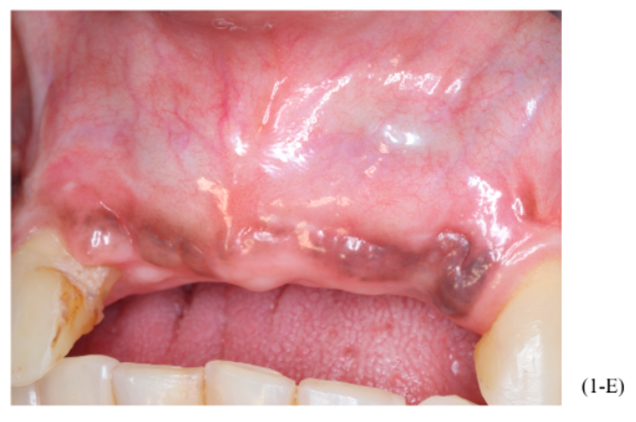

Figuras A,B,C, D e E – Imagens evidenciando grande perda óssea anterior no sentido horizontal, bem como a vestibularização do rebordo anterior, o que impossibilita a instalação dos implantes em um bom posicionamento tridimensional.

Foram planejados três implantes do tipo Cone Morse Maestro Implacil De Bortoli 3.5 x 13 mm. Após remoção de maneira facilitada dos parafusos tenda, foram instalados três implantes em ótimo posicionamento tridimensional (imagens 1-E, 1-F, 1-G, 1-H). Todos apresentaram estabilidade primária de 35 Ncm de torque e aguardamos quatro meses para posterior reabilitação protética definitiva com próteses individualizadas de metalocerâmica do tipo parafusada.